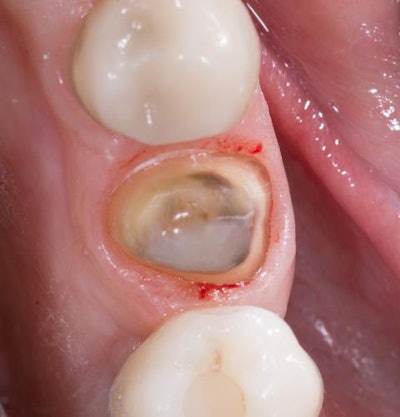

Once the failing amalgam was completely removed and the mesial caries excavated, Kuraray's Caries Detector was applied to assist in verification of complete caries removal. A composite buildup was placed using Clearfil Universal Bond Quick (Kuraray Noritake) and composite resin (figure 2, below).

Clearfil Universal Bond Quick is just as its name indicates: universal and quick. It was chosen for its ease of use without compromised strength. It was used for bonding of the composite buildup and again later for bonding of the Katana STML A3 crown (Kuraray Noritake) with Panavia SA Cement Universal (Kuraray Noritake) translucent cement.